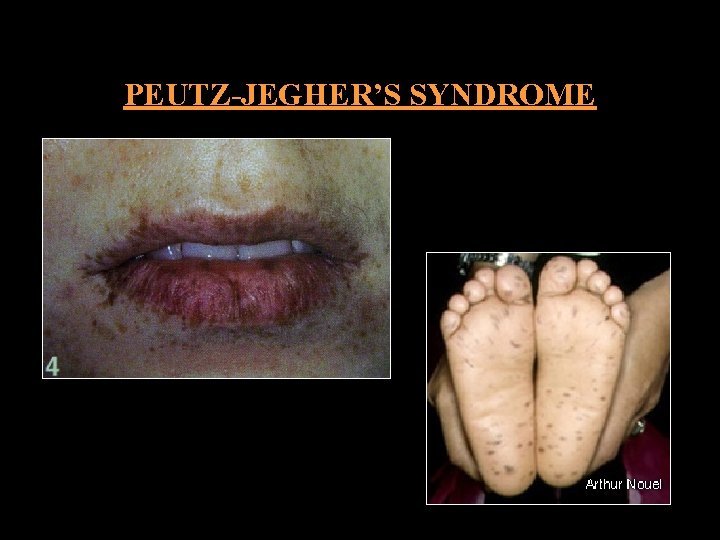

PEUTZ-JEGHER’S SYNDROME HEREDITORY INTESTINAL POLYPOSIS SYNDROME CLINICAL FEATURES: • SEX Equally • SITE Intestinal polyps ORAL MANIFESTATION: • SITE BM, gingiva, tongue, hard palate • SYMPTOMS Abdominal pain • AGE from birth • COLOR Bluish black macules • Multiple melanotic brownish • SIZE 1 -5 cm • Facial pigmentation macules around lips • SIZE 0. 5 cm

PEUTZ-JEGHER’S SYNDROME